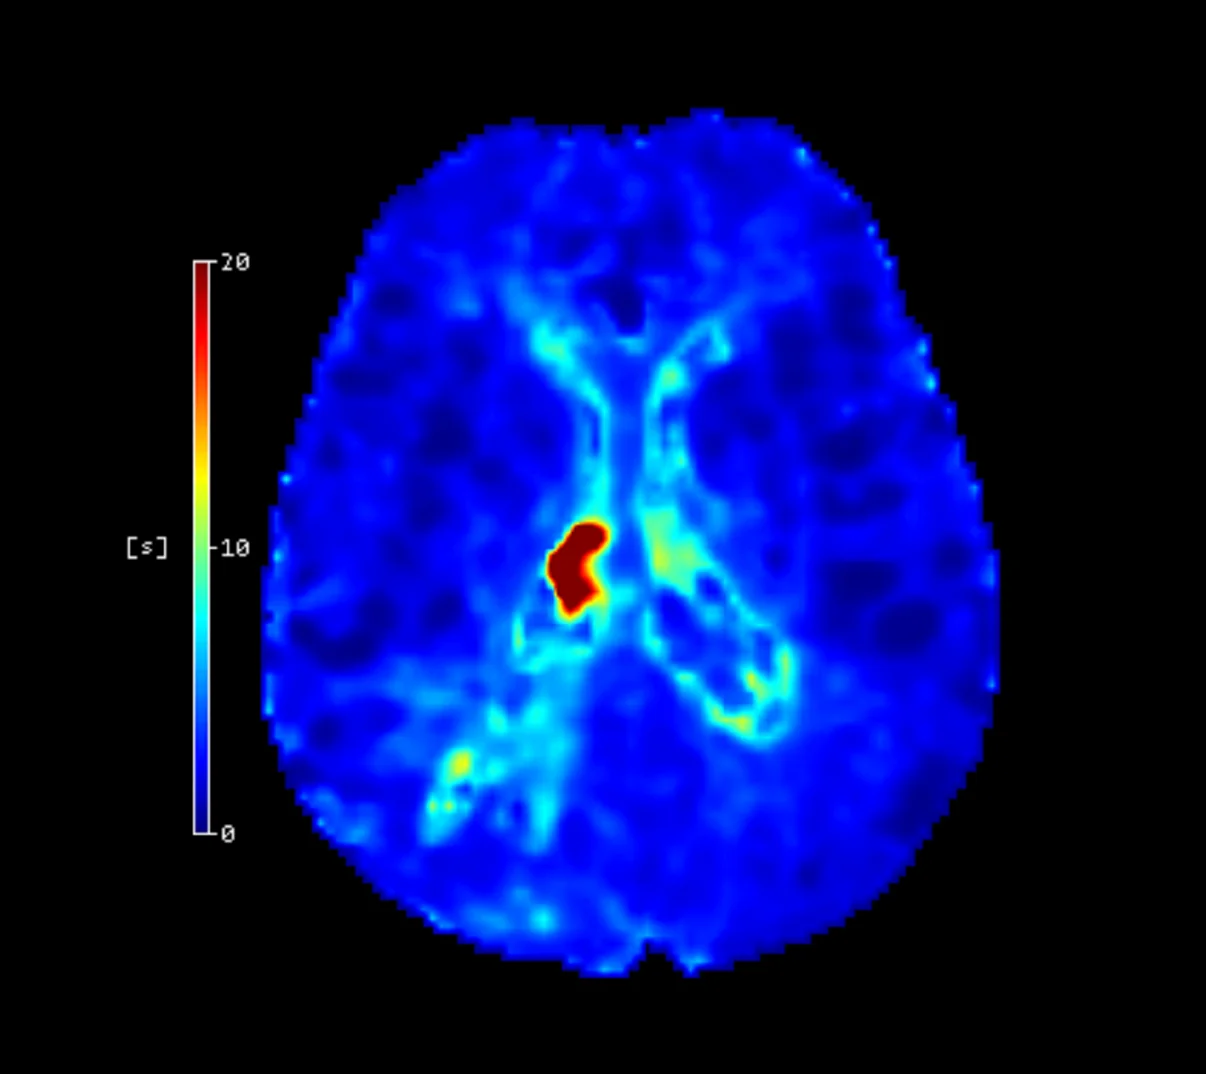

Cercare Medical Neurosuite Stroke yazılımı, CT ve MR perfüzyon verilerinden elde edilen Tmax (perfüzyon gecikmesi) ve CBF (beyin kan akımı) parametrelerini birlikte değerlendirerek, infarkt çekirdeği ve penumbra (kurtarılabilir beyin dokusu) ayrımını yapar. Tmax > 6 sn eşik değerinin düşük CBF (<30) ile birlikte analiz edilmesi, geri dönüşümsüz hasarın yüksek doğrulukla belirlenmesini sağlar. Bu yaklaşım, klinisyenlere hangi hastaların tromboliz veya trombektomi tedavisinden fayda görebileceğini dakikalar içinde netleştirme imkânı verir*.

Eşik Değer Tabanlı Lezyon Kantifikasyonu

Cercare Medical Neurosuite Stroke yazılımının gelişmiş paketinde yer alan eşik değer tabanlı lezyon kantifikasyonu, perfüzyon parametrelerinin belirlenmiş klinik eşik değerlerle karşılaştırılması yoluyla çalışır. Özellikle Tmax, CBF ve CBV gibi parametreler için literatürde yaygın olarak kabul gören cut-off değerleri kullanılarak, çekirdek infarkt (geri dönüşsüz doku) ve penumbra (kurtarılabilir doku) hacimleri sayısal olarak hesaplanır.

Bu kantifikasyon sayesinde radyolog ve nörologlar, lezyon boyutunu ve konumunu mililitre (mL) cinsinden objektif bir şekilde değerlendirebilir. Klinik araştırmalar, bu yöntemle elde edilen kantitatif analizlerin, görsel yorumlamaya kıyasla hasta seçiminde tutarlılığı %25’e kadar artırdığını ve tedaviye uygunluk kararlarını hızlandırdığını göstermektedir*.